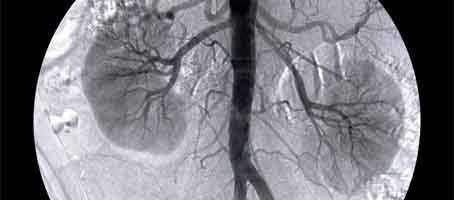

End-stage kidney failure is most commonly caused by diabetes, and often requires a kidney transplant. Careful management of blood pressure and blood glucose levels can half the risk of kidney disease.